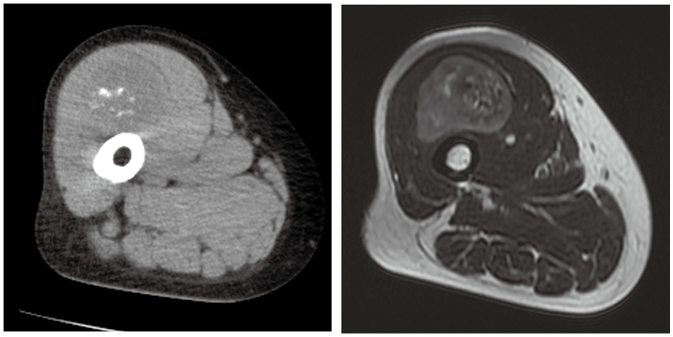

症例1

70歳代,女性。

約1年前から緩徐に増悪する右大腿部の腫脹を主訴に受診。CTおよびMRIを施行した。

乳癌,子宮体癌術後。